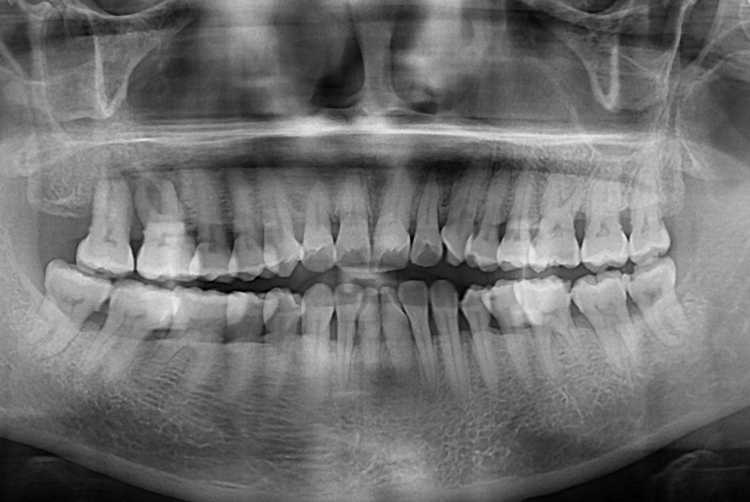

[임플란트] 어금니 임플란트

치료전 : 2019-04-29

세종치과는 많은 환자와 다양한 케이스를 바탕으로

항상 편안한 임플란트 수술을 제공하고자 노력하고,

오래동안 튼튼히 쓸 수 있는 임플란트 수술을 가장 큰 목표로 삼고 있습니다.